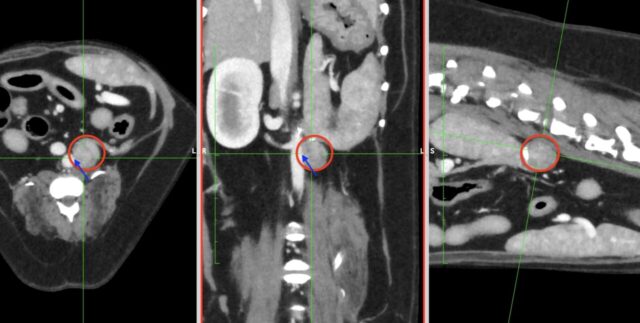

画像検査(エコー検査やCT検査)では確定することはできませんが、褐色細胞腫を疑うことは可能です。

・CT検査:がんの大きさや広がり、リンパ節転移、遠隔転移(肝臓、肺など)の評価

※CT検査はより綿密な治療方針を決定するうえで必須の検査です

褐色細胞腫のCT画像(赤丸:副腎褐色細胞腫、青矢印:動脈)